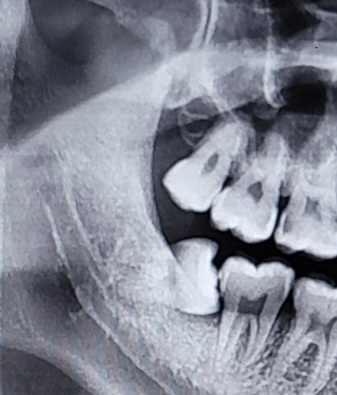

매복사랑니에 대한 문의시군요.

사랑니가 정상적으로 나와서 청결하게 유지된다면 어금니로 사용할 수 있겠지만 매복 형태로 자라는 경우에는 관리의 어려움이 많아 감염 및 통증의 원인이 되고, 인접 치아에 손상을 주는 등 여러가지 문제를 유발할 수 있기 때문에 발치를 권하는 경우가 많습니다.

따라서 사랑니 경험이 많은 구강악안면외과 전문의와 충분히 상의해 보시고 발치 여부를 결정해 보시길 바랍니다. 매복 사랑니 발치후 1-2주간은 통증 및 불편감이 있을 수 있으므로, 발치 후 처방받은 약을 잘 드시면서 잘 관리 해주시기 바랍니다.